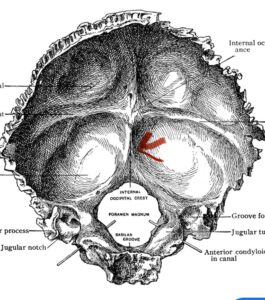

Although some patients do not require a decompression and just require an occipital cervical fusion, most require some sort of decompression of the neural elements. After a decompression an instrumented fusion is performed. A useful anatomic structure for anchoring the top portion of the construct to the skull is the midline keel of the subocciput. This structure extends from the external occipital protuberance, which corresponds to the confluence of the sagittal and transverse sinuses, to just above the foramen magnum:

(Fig. 1). This bone is quite thick, about 15 mm (Figs. 2a and b). Most modern plate systems utilize three midline keel screws with the option to place within a 2 cm lateral fixation point. This plate is connected to sometimes tricky-to-bend rods and connected to screw fixation points in the cervical spine (Fig. 3). Bone graft material extends from skull to cervical spine.

Fig. 2a: Cartoon illustrating posterior projection of internal skull structures demonstrating the midline keel in the subocciput above the foramen magnum.

Fig. 2b: Axial CT scan of the brain demonstrating the thickness of the midline keel (red arrow) compared to the more lateral subocciput (red dot) making the keel ideal place for screw fixation